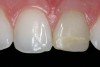

Replacement of existing restorations is responsible for 75% of all operative dentistry.15,19 The reasons for placement and replacement of restorations of direct restorative materials include: primary caries (Figure 1 and Figure 2); recurrent caries (Figure 3); poor margins (Figure 4 and Figure 5); restoration fracture (Figure 6 and Figure 7); tooth fracture (Figure 8); esthetics (Figure 9); non-carious tooth structure lost (attrition, abrasion, abfraction, erosion) (Figure 10); and pain/sensitivity.

Figure 2  Initial caries. Class III and V carious lesions.

Figure 2